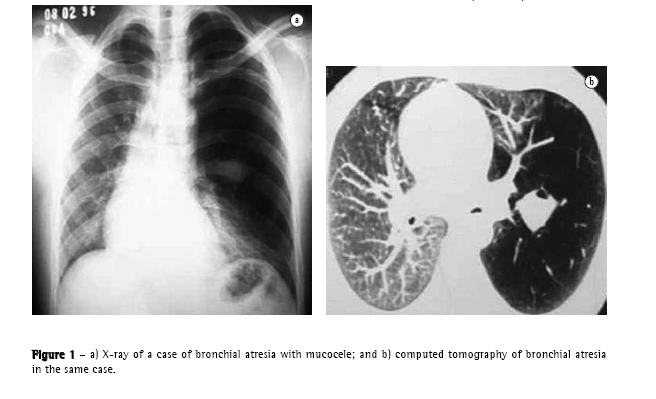

There are four principal causal mechanisms that can participate, together or in isolation, in the development of emphysema: hypoplasia (Figure 1), atrophy, hyperdistention, and partial or total destruction of the alveoli. Hypoplasia occurs due to failure in the development of the alveoli. Atrophy results from atrophy of alveolar walls, of former normal development. Hyperdistention represents distention of the alveoli beyond its normal capacity at maximum inspiration. Destruction is represented by loss of substance of alveolar walls, anatomopathologically distinct from atrophy.

The yield of conventional chest X-ray in the evaluation of emphysema is quite limited. When there is no significant air trapping, the principal alteration is reduction of vasculature, which is only perceived too late in the natural history of the disease, and is an extremely subjective criterion. When there is air trapping (Figures 3 and 4), the criteria are safer, and can be divided into 3 basic groups of alterations,(6,8) presented in Chart 1. When all criteria are present, the diagnosis is definitively confirmed. It should be noted that the increased right chambers of the heart, with reduction of the intrasegmental vasculature, can also be identified in pulmonary arterial hypertension, without emphysema. It should also be noted that bullae are only present in approximately one-third of the cases.